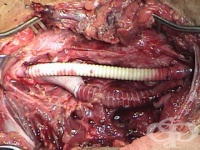

S85.5 Травма на vena poplitea

Подколенната вена се намира в задколянната ямка. Травма на vena poplitea се получава най-често при п...